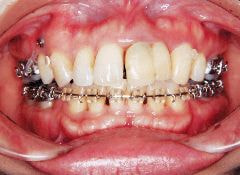

治療例1 (インプラント補綴+矯正)